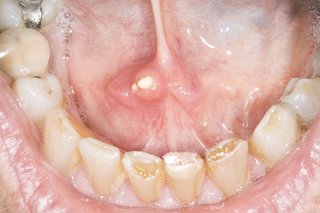

The inside of a person's mouth showing their lower teeth and part of their bottom lip. There is a small, white salivary gland stone under their tongue.

They vary in size, but most are as big as a pea.